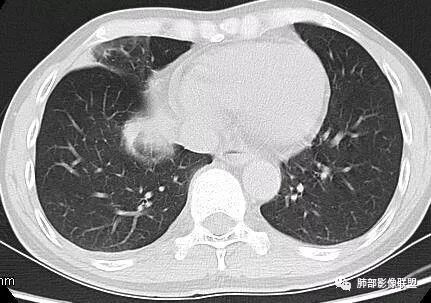

南边:深分叶、大肿块

南边:主体在下叶前基底段

南边:边缘膨隆

南边:中叶、下叶背段支气管推移

南边:中叶支气管腔内似有粘液栓,外侧段有炎性病变

南边:有老师问为啥考虑中叶支气管受压?不是支气管来源的?

1、主体病灶在下叶

2、支气管腔还在,有移位

南边:病灶边界清,提示侵袭性弱,膨胀生长为主;这时候我们提示病灶不应该是支气管关系密切,提示间叶来源或胸膜来源

深分叶,警惕恶性